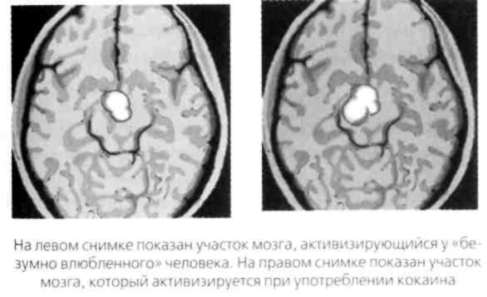

Ниже показаны результаты сканирования мозга «безумно влюбленного» человека и кокаинового наркомана. Убедитесь, что они почти идентичны.

Иллюстрация к книге — Почему мужчины хотят секса, а женщины любви [Why-do-men-want-sex-women-love-03.jpg]

Итак, влюблены ли вы или просто приняли наркотик, ваши ощущения будут одинаковыми. Сканирование также показывает, что у матерей, которые смотрят на своих младенцев, проявляется та же мозговая активность, что и у людей, глядящих на своих любимых. Бартельс и Зеки сделали вывод о том, что романтическая и материнская любовь связаны с продолжением рода, поскольку и любимый человек, и младенец обещают сохранение ДНК.